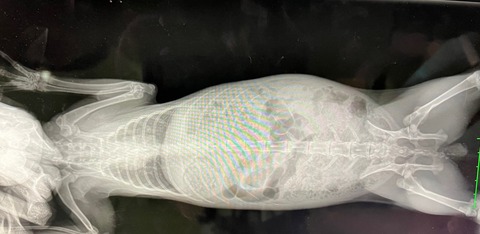

12月4日、ドナちゃん避妊手術しました。

※白血球の上昇などはストレス起因と判断できるレベル、と、

血小板は機械の誤作動による、顕微鏡で別途確認済

奥歯も問題なし。

術前の血液検査、レントゲン、いずれも問題ありません。